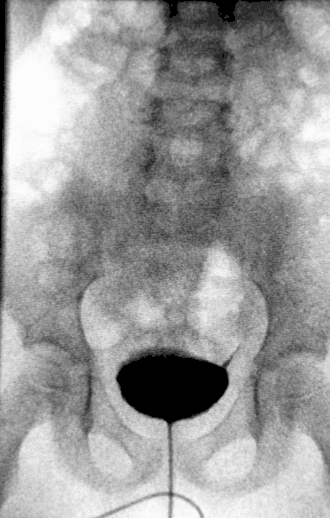

![]() Урограмма почек, пораженных гидронефрозом | |

Диагноз ставится на основании УЗИ, экскреторной урографии и ренографии.